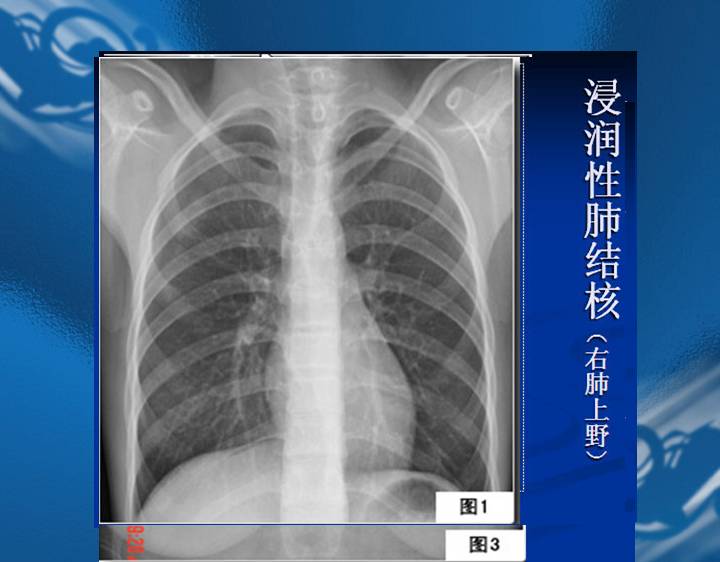

执业医师资格考试“实践技能”影像学辅导资料